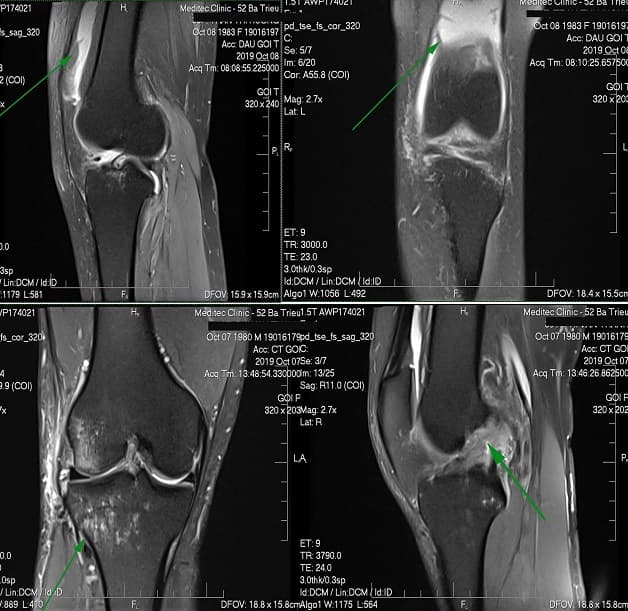

– MRI cơ xương khớp

MRI vùng này cho thấy cấu trúc cơ, dây chằng, sụn, xương, tủy xương, mỡ, mạch máu, giúp kiểm tra khớp gối, khớp háng, khớp vai, khớp khuỷu, khớp cổ tay, khớp cổ chân.